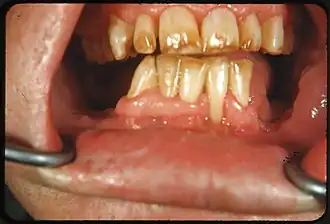

Fluorosis dental

![]() Manchas de color blanco o café en la superficie dental. | ||

Dependiendo del nivel de fluoruro en el agua, el aspecto de los dientes moteados, puede variar: 1) Cambios caracterizados por manchas de color blanco en el esmalte, 2) Cambios moderados manifestados por áreas opacas blancas que afectan más el área de la superficie dental. 3) Cambios moderado e intensos que muestran formación de fosetas y coloración parda de la superficie e incluso: 4) Apariencia corroída.

Los dientes afectados moderada o intensamente pueden mostrar tendencia a desgastar, e incluso fracturar, el esmalte. Algunos estudios demuestran que estos dientes presentan dificultades para sostener las restauraciones dentales.